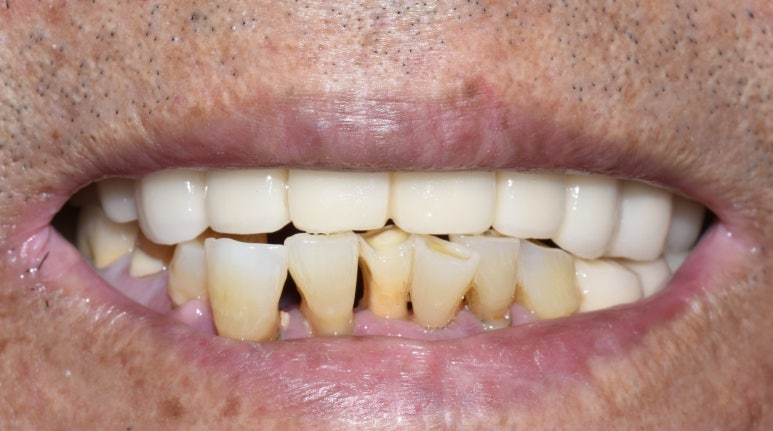

- 위의 틀니와 아래 어금니 임플란트를 5년쓰시다가

어금니 임플란트가 너무 편하고 뺐다 꼈다하는 틀니가 귀찮다고 하셔서 위 전체 임플란트

-

원래 치아상태 ->2. 위 틀니, 하악어금니 임플란트 ->3. 상악도 전체 임플란트로.